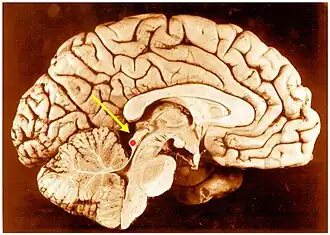

![]() Inferior colliculus (red dot) in human brain, sagittal section. | |

The inferior colliculus (IC) (Latin for lower hill) is the principal midbrain nucleus of the auditory pathway and receives input from several peripheral brainstem nuclei in the auditory pathway, as well as inputs from the auditory cortex.[1] The inferior colliculus has three subdivisions: the central nucleus, a dorsal cortex by which it is surrounded, and an external cortex which is located laterally.[1] Its bimodal neurons are implicated in auditory-somatosensory interaction, receiving projections from somatosensory nuclei. This multisensory integration may underlie a filtering of self-effected sounds from vocalization, chewing, or respiration activities.[1]

The inferior colliculi together with the superior colliculi form the eminences of the corpora quadrigemina, and also part of the midbrain tectum. The inferior colliculus lies caudal to its counterpart - the superior colliculus - above the trochlear nerve, and at the base of the projection of the medial geniculate nucleus and the lateral geniculate nucleus.